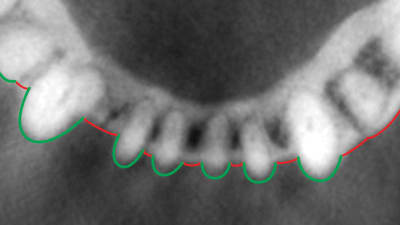

Online Only Online Only Is Gingival Recession a Consequence of an Orthodontic Tooth Size and/or Tooth Position Discrepancy? A Paradigm Shift By Colin Richman, DDS, DMD August 01, 2010 25 min read